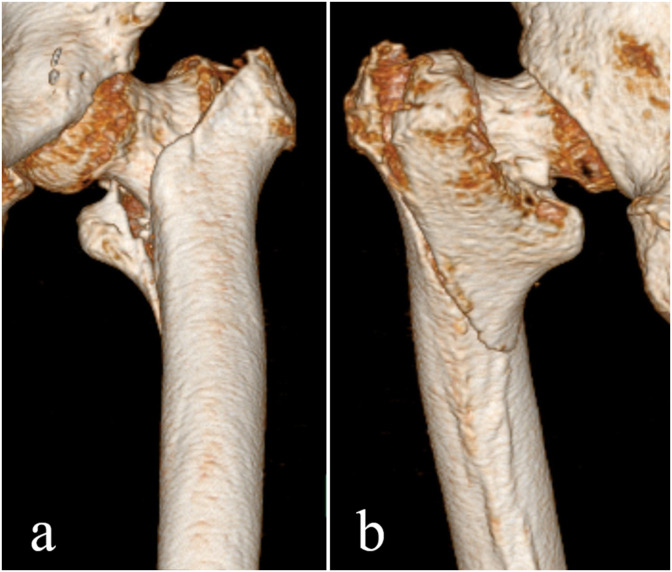

After transfer to our hospital, the patient was reassessed carefully. There were no complaints of cough, dyspnea, or taste disorder. However, mild dementia was noted. Before the injury, she was able to walk with a cane. On physical examination, a shortened externally rotated left lower extremity with no peripheral neurovascular deficit was evident. Her vital signs on admission were as follows: blood pressure, 136/88 mmHg; heart rate, 84 beats/min; body temperature, 37.1 °C; respiratory rate, 18 breaths/min; and oxygen saturation with room air, 90%. A chest radiograph did not demonstrate any lung abnormalities except for a cable at the site of the previous cardiac surgery and marked cardiac enlargement. Computed tomography (CT) revealed diffuse trivial pulmonary edema in both lungs (Fig. 1 ). There were no ground grass opacities, crazy-paving patterns, or any other findings that assumed COVID-19 [10]. Radiographs of the left hip revealed a pertrochanteric fracture with features consistent with three-part fragments (AO 31A2.2, Fig. 2 ). Three-dimensional CT showed a large oblique fragment consisting of the greater trochanter and the lesser trochanter (Shoda classification [11]; three-part G-L) (Fig. 3 ). PCR analysis for COVID-19 was again performed on admission, and the test result was positive.

Fig. 3.

Three-dimensional computed tomography shows a large oblique fragment of the greater trochanter including the lesser trochanter. (a) Anterior side, (b) posterior side.

In the present case, a large oblique fragment of the greater trochanter, including the lesser trochanter, was shown. Unstable trochanteric fractures may exhibit (1) posteromedial large separate fragmentation, (2) a basicervical pattern, (3) a reverse obliquity pattern, (4) a displaced greater trochanter (lateral wall fracture), or (5) the inability to be reduced before internal fixation [11]. Of the above characteristics, three-part G-L-type fracture is considered to have posteromedial large separate fragmentation. For this type of unstable fracture, we have corrected to a positive anterior-posterior cortical position combined with a positive/neutral lateral position on fluoroscopy to obtain cortical support [23]. Although surgical invasion should be minimized in COVID-19 patients, optimal surgical reduction should be performed. Even in the short term, the fracture was stable and there were no symptoms associated with the fracture.